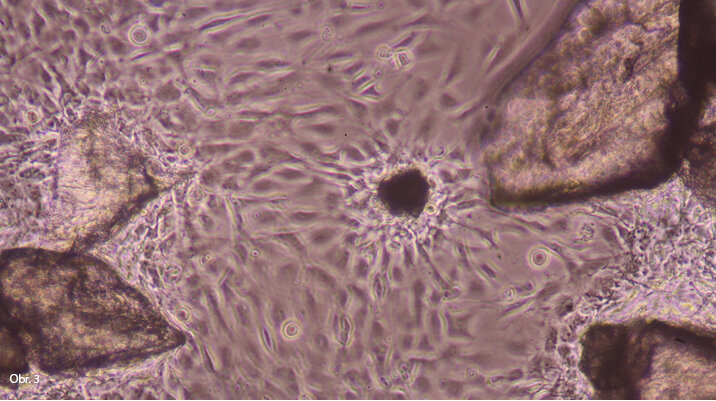

Rozemletá tvrdá zubní tkáň ve zkouškách in vitro s buňkami MG63. Je vidět afinita buněk k některým zrnům tvrdé zubní tkáně.

Afinita k zrnům tvrdé zubní tkáně je vidět na zrnu, které je obaleno buňkami. Předpokládáme, že toto zrno je dentin. Velké zrno v pravé části obrazu je bez buněčného obalu. Předpokládáme, že jde o sklovinu.